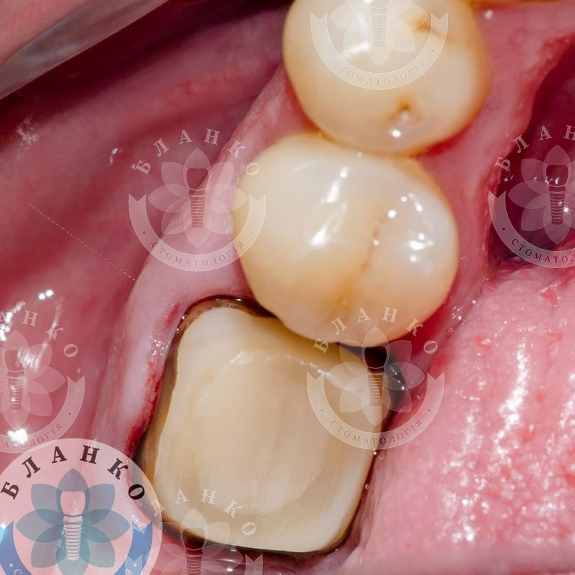

— твердые ткани зуба восстановлены с помощью специального материала

— сняты оттиски и изготовлена высокопрочная, гипоаллергенная и высокоэстетичная коронка из диоксида циркония.